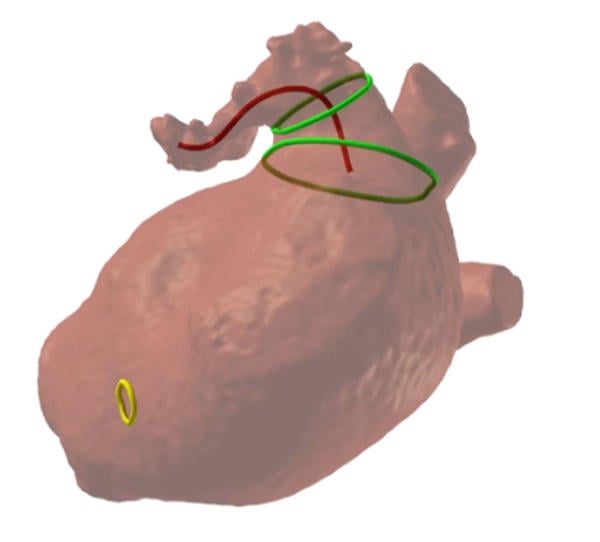

LAA closure - morphology

LAA closure - CT reconstruction

LAA closure by AMULET - FEops model

Diagnostic workup: cardiac CT reconstruction

- Cardiac CT allowed for reconstruction by FEops software modelling

- TOE was also available for pre-planning given the complex inferior chicken wing morphology